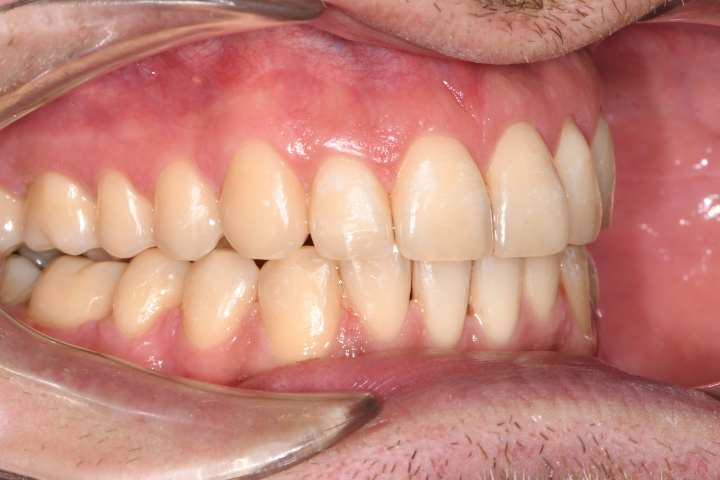

Az elmúlt évekből rengeteg szakmai referenciát tudnánk bemutatni, amelyek különböző fogszabályozási problémákat oldottak meg. Válogatva a több száz esetből, ezen az oldalon olyan képeket, információkat igyekeztünk bemutatni, amelyeknek a segítségével a jövőbeni pácienseinknek azt tudjuk üzenni: A Te fogsorod is lehet gyönyörű!

(Képeket a Pácienseink külön írásos beleegyezésével mutatjuk be!)